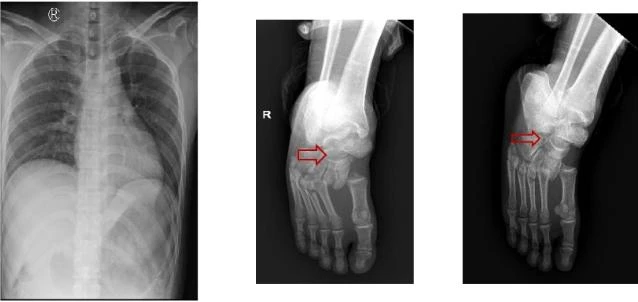

Chụp X quang cho thấy nhiều xương ngực và chân phải anh H. bị gãy. Ảnh: BVCC |

Anh H. được đưa tới BV trong tình trạng tỉnh, tiếp xúc được, tim đều, phổi trong, bụng mềm. Tuy nhiên, anh bị liệt hoàn toàn 2 chân và bí tiểu.

Anh K. được đưa vào BV trong tình trạng tỉnh, tiếp xúc được, tim đều, phổi trong, bụng mềm. Tuy nhiên, anh K. bí tiểu và đau cột sống thắt lưng, liệt hoàn toàn 2 chân.